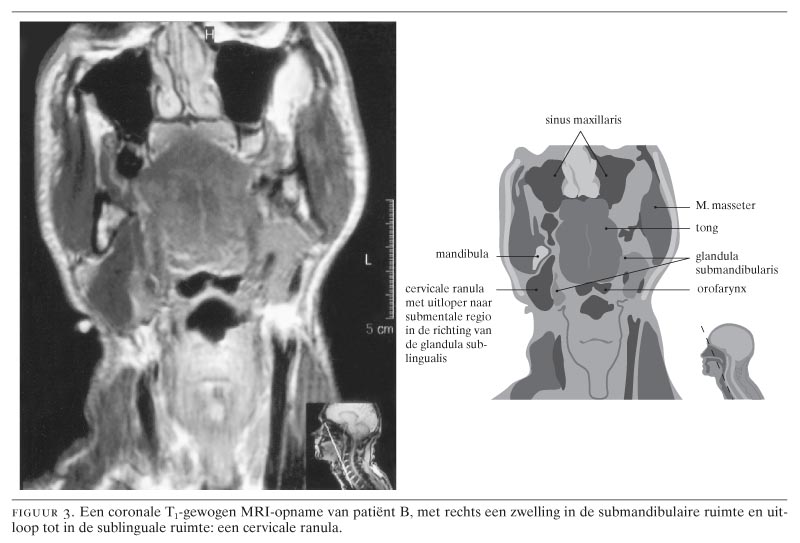

Drie patiënten, 2 mannen van 21 en 39 jaar en 1 vrouw van 29 jaar, presenteerden zich met een unilaterale zwelling in de hals zonder begeleidende symptomen. Bij de jongste man werd de diagnose ‘cervicale ranula’ (‘plunging ranula’) gesteld nadat bij (herhaalde) punctie een helder gelig taai secreet was verkregen met een hoge amylaseactiviteit. Bij de oudste man kwam deze aandoening tijdens een halsexploratie aan het licht en bij de vrouw pas na 2 operatieve ingrepen. Bij alle 3 trad er na verwijdering van de betreffende speekselklieren geen recidief op. Een cervicale ranula is een uitbreiding van een pseudo-cyste van de glandula sublingualis. Belangrijke aanwijzingen daarvoor zijn: een gelijktijdig of in het verleden aanwezige ranula in de mondbodem, een op de MRI- of CT-scan zichtbare cysteuze massa in de submandibulaire ruimte met een uitloper naar de sublinguale ruimte en een verhoogde amylaseactiviteit in punctiemateriaal. De behandeling bestaat uit het elimineren van het speeksel door extirpatie van de glandula sublingualis, waarbij de cervicale component intraoraal wordt gedraineerd. Vanwege het pseudo-cysteuze aspect van de zwelling in de hals is lokale excisie van een cervicale ranula zinloos.